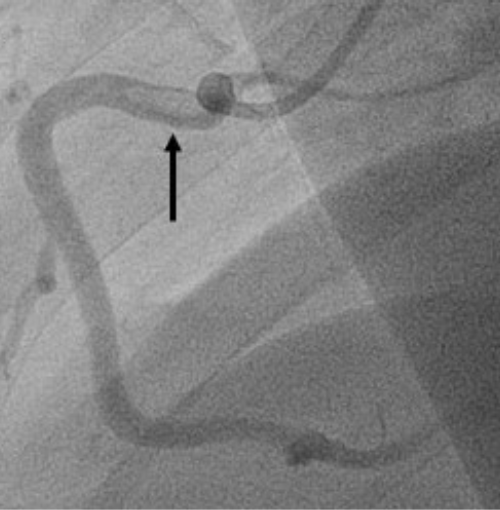

A 52-year-old man presented acutely with inferior ST-segment elevation myocardial infarction (STEMI). The left coronary system was unobstructed. The right coronary artery had Thrombolysis in Myocardial Infarction (TIMI) grade 3 flow throughout; however, angiography demonstrated a hazy oval filling defect proximally consistent with a large intracoronary thrombus (Figures 1A-1C). Given that the ST elevation was resolving and acknowledging the risk of distal coronary and/or systemic embolism, we deferred further intervention. The patient was transferred to the Coronary Care Unit on quadruple antithrombotic regime (aspirin, ticagrelor, tirofiban infusion for 48 hours, and enoxaparin). Transthoracic echocardiography demonstrated preserved systolic function.